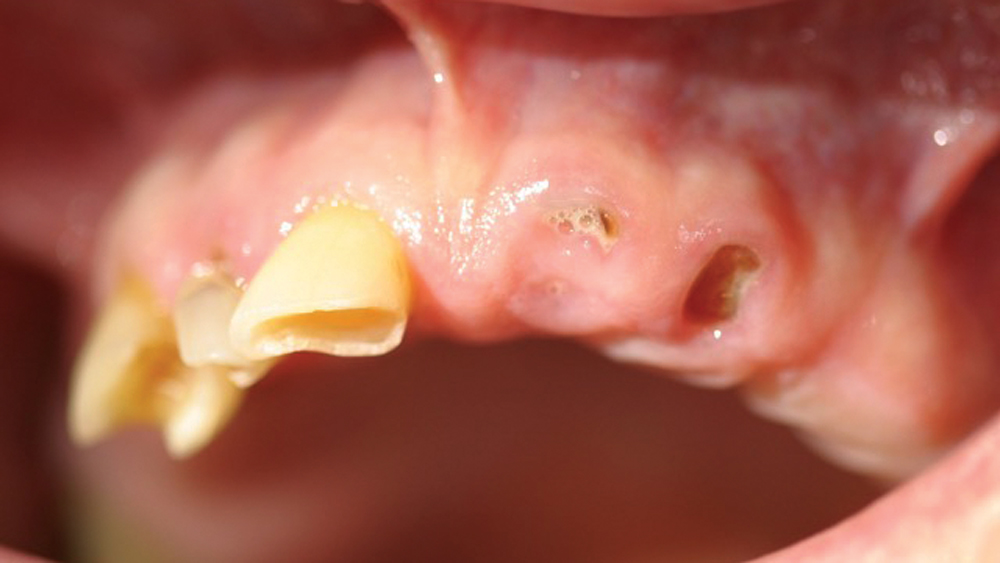

Patients who present with terminal dentition commonly suffer from discomfort, poor dental function and low self-esteem as a result of their condition. Immediate implant placement is a treatment option that offers instant, life-changing benefits for these patients while setting the stage for a predictable long-term outcome. In the presence of sufficient bone quality and volume, after atraumatically extracting the patient’s teeth, implants can be placed and a temporary appliance delivered, allowing the patient to walk out of the office with dramatically improved form and function in one appointment. This immediately enhances the patient’s quality of life and provides a significant “wow” factor for your practice.

The following case demonstrates how to immediately place implants in full-arch indications. By properly positioning the implants, maximizing primary stability and providing the most durable restoration possible, the short- and long-term needs of the patient are addressed in an efficient, predictable manner.